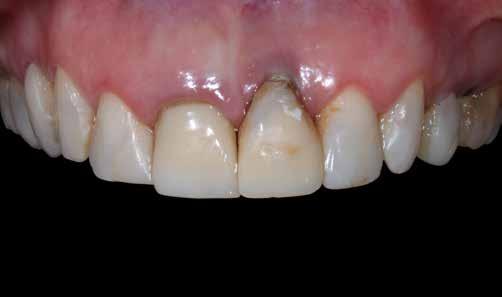

A rendelésünkön egy 34 éves latin-amerikai nőbeteg azzal a panasszal jelentkezett, hogy a fogait „túl rövidnek” találja, és ezen felül a mosolyával sem volt megelégedve. Az anamnézisfelvétel alapján egészséges volt, elmondása szerint rendszeresen járt orvoshoz. Öt évvel korábban néhány hátsó fogát restaurálták. Páciensünk szájhigiénéje megfelelő volt,

a fogait rendszeresen ápolta. House klasszifikációja szerint, amely a pácienseket a fogászati kezelésekhez való attitűdjük szerint négy csoportba sorolja, a páciensünk a szabálykövető csoportba tartozott.

Az előzetes állapotfelmérést és a kezelés megtervezését követően a fogakat minimál invazív módon preparáltuk (1. a-b ábrák), majd az előkészített fogak ínybarázdáiba fonalbehelyező eszköz segítségével (113 Serrated Gingival Cord Packer, Hu-Friedy, Chicago, Illinois) teflonszalagot helyeztünk (Loctite Thread Seal Tape, Henkel Loctite Corp., Egyesült Államok), (1. c ábra). A hagyományos retrakciós fonalak helyett, a rugalmasságuk miatt előnyösebbnek tartjuk a teflonszalagok használatát. A kofferdámot (Dental Dam, Nic Tone, Bukarest, Románia) az előkészített fogakon kívül, az azoktól disztálisan elhelyezkedő egy-egy fognak megfelelően is perforáltuk.

Az oxigén inhibíciós réteg kialakulásának elkerülése érdekében a kerámiafelszíneket glicerin géllel (Liquid Strip, Ivoclar Vivadent, Schaan, Liechtenstein) borítottuk, majd ezeket a felszíneket ismét 20-20 másodpercen keresztül világítottuk. A végeredmény megfelelt a páciens esztétikai igényeinek (6. a. ábra). Az átadott restaurátumok épségének megőrzése érdekében, a páciens számára éjszakai fogvédő sín készült. Az ötéves kontroll alkalmával megállapítottuk, hogy az elvégzett kezelésünk továbbra is sikeresnek tekinthető (6. b. ábra)